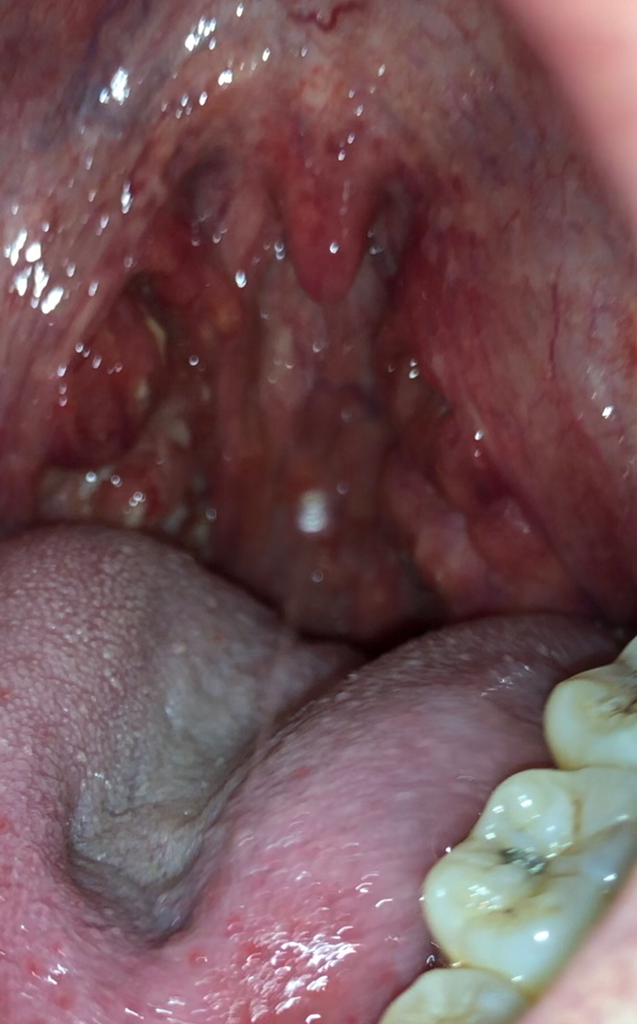

편도염인가요 편도결석인가요??

근데 결석처럼 보이는 노란색이 보이는데

결석같지가 않고 염증처럼 보여서요

올려주신 사진은 편도 결석이 생각됩니다.

편도 혹은 편도선에 있는 작은 구멍들에 음식물 찌꺼기와 세균이 뭉쳐서 생기는 쌀알 크기의 작고 노란 알갱이를 말하며 결석이라고 하나 돌처럼 딱딱하지 않습니다.

사진이 흐릿하지만 편도의 염증성 병변으로 보입니다. 수술 전 음주, 흡연 금하시고 감기 조심하시기 바랍니다.

편도염처럼 보입니다